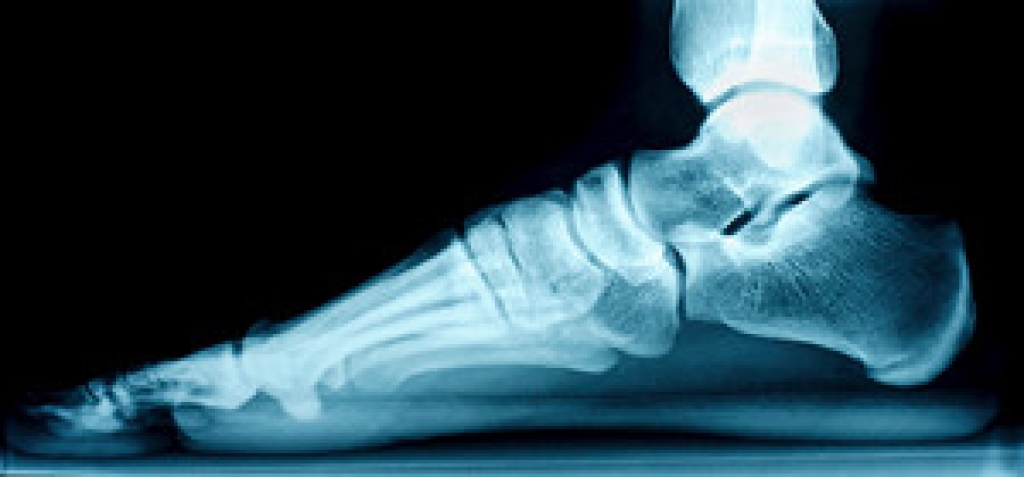

Flat feet, or fallen arches, are a common condition where the arches of the feet collapse, causing the entire sole to touch the ground. Recognizing the symptoms of flat feet is essential for understanding and addressing this condition. One prevalent sign is pain or discomfort along the inner side of the ankle and arch. Individuals with flat feet may also experience swelling along the inside of the ankle. The lack of a visible arch when standing or walking is a visual indicator of flat feet. Overpronation, where the foot rolls inward excessively, can contribute to this condition and lead to related issues, including shin splints or knee pain. Fatigue and aching in the feet and legs can occur, especially after prolonged standing. If you have flat feet, it is suggested that you speak to a podiatrist who can provide you with effective relief options.

Flatfoot is a condition many people suffer from. If you have flat feet, contact Dr. Richard DiMario from Maine. Our doctor will treat your foot and ankle needs.

What Are Flat Feet?

Flatfoot is a condition in which the arch of the foot is depressed and the sole of the foot is almost completely in contact with the ground. About 20-30% of the population generally has flat feet because their arches never formed during growth.

Conditions & Problems:

Having flat feet makes it difficult to run or walk because of the stress placed on the ankles.

Alignment – The general alignment of your legs can be disrupted, because the ankles move inward which can cause major discomfort.

Knees – If you have complications with your knees, flat feet can be a contributor to arthritis in that area.

Symptoms

Treatment

If you are experiencing pain and stress on the foot you may weaken the posterior tibial tendon, which runs around the inside of the ankle.